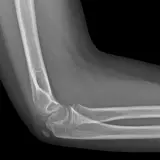

Over 2,100 interactive radiology cases, curated by radiologists for your level of training. Scroll, window, and view cases full screen — just like on PACS. Click linked findings in each writeup to jump straight to them on the image. Cases include sample reports, a focused discussion section, original illustrations, and videos.

Casos totalmente interactivos con las herramientas que esperaría de un PACS: scroll, ventana, zoom, pan, mediciones, ROI y modo de pantalla completa.

• Anotaciones enlazadas

Anotaciones extensas resaltan los hallazgos clave directamente sobre los casos. Haga clic en los hallazgos enlazados dentro de la descripción del caso para saltar a su ubicación exacta en el estudio.

Desplace, arrastre, ajuste ventana y amplíe como en una estación PACS de trabajo

Aprenda con eficiencia gracias a hallazgos de imagen anotados e ilustraciones